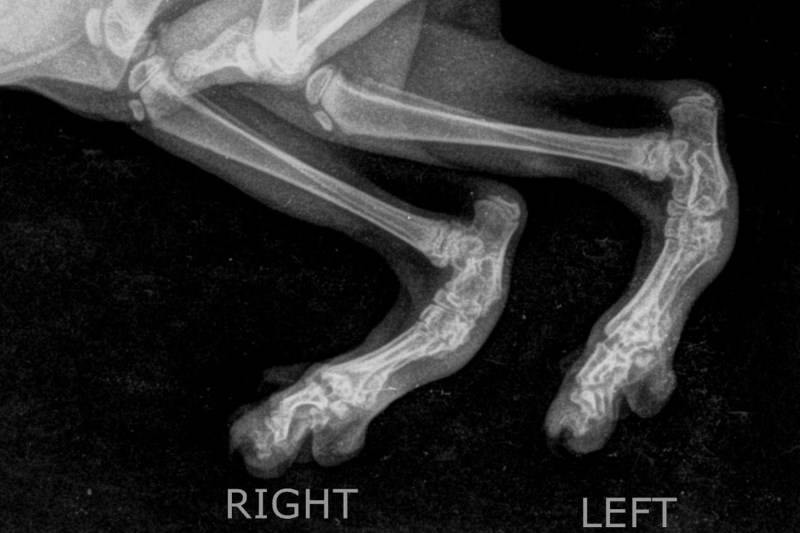

Рентген лап

После внешнего осмотра берут анализы крови и других биологических жидкостей, при необходимости проводят кардиограмму, чтобы оценить работу сердца. Для оценки повреждения конечности врач проводит МРТ или рентгенологическое исследование, чтобы проверить наличие переломов, вывихов и ушибов. Если диагноз подтвердится, припухлую конечность обрабатывают и назначают лечение.